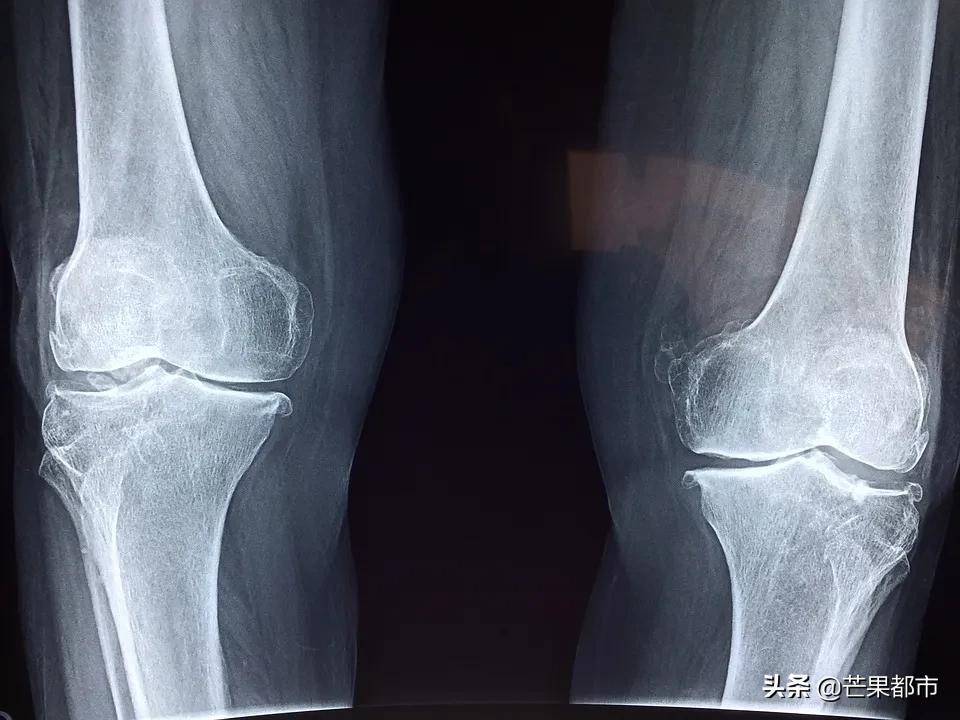

湖南省儿童医院 骨科 副主任医师 严安: 通过影像学的检查,评估他的右胫骨,就是小腿的病变程度到了哪一步,通过磁共振的检查发现,他还有脓肿没有清除,所以我们急诊给他安排了手术。

目前通过手术治疗后,孩子病情得到明显缓解。医生表示, 骨髓炎好发于长骨,糖尿病患者的足部或由于外伤或手术引起的穿透性骨损伤部位。 儿童最常见部位为血供良好的长骨,如胫骨或股骨的干骺端。